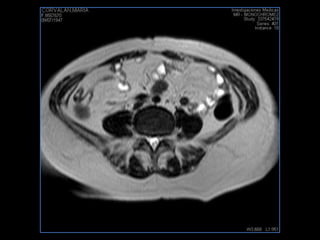

LIC ALEJANDRA GALVEZ RM DE ABDOMEN

PROTOCOLO pelvis SAG T2, Y FAT SAT (FINOS) AXIAL T1  AX FAT SAT CON   GADOLINIO :  AX T1 Y COR T1 SAT: NO  FASE: RL THK: 3MM  COIL:  GAP: (FACTOR 1.4) 1MM FOV: 40 CM NEX:2 SINCRONIZACION RESPIRATORIA EN 3 O 4 CICLOS ALE

resonancia de abdomen